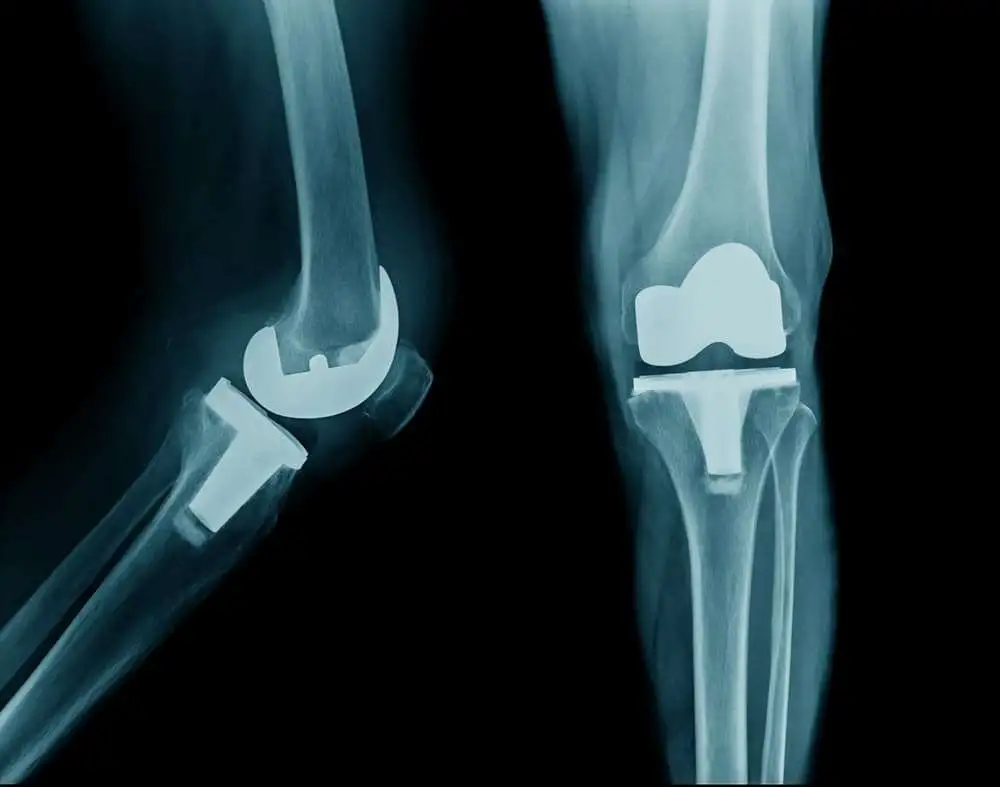

Total knee arthroplasty has been linked to severe postoperative pain which can limit the recovery and extend the length of stay in the hospital. However, due to surgery's financial pressures and stress on improving patient satisfaction, scientists focus on to design other outpatient and short-stay programs for patients undergoing total knee arthroplasty.

Recently, Chris Cullo & Jonathan T. Weed conducted a review study to evaluate the efficacy of new therapeutic programs in patients undergoing total knee arthroplasty. The study revealed that the outpatient and short-stay programs comprise specific factors which help in making the procedure more beneficial than the traditional methods. One of the main factors involved was an effective perioperative anesthetic plan.  Perioperative anesthesia helps to enhance comfort & safety of patients during surgery. Further, for smoother & quicker postoperative course, improved technology & innovation played a significant role. These technologies provided more efficient strategies than the traditional ones. There was a significant reduction in post-operative pain due to peripheral nerve block usage in connection with a variety of systemic analgesics.  The adductor canal and IPACK blocks have emerged as a popular technique due to its considerable analgesic efficacy and muscle sparing properties.